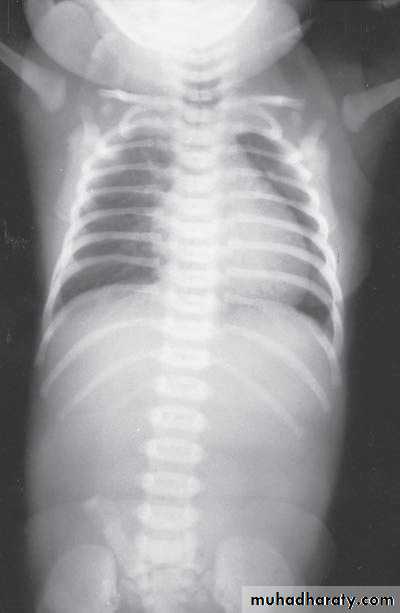

Scaphoid abdomen